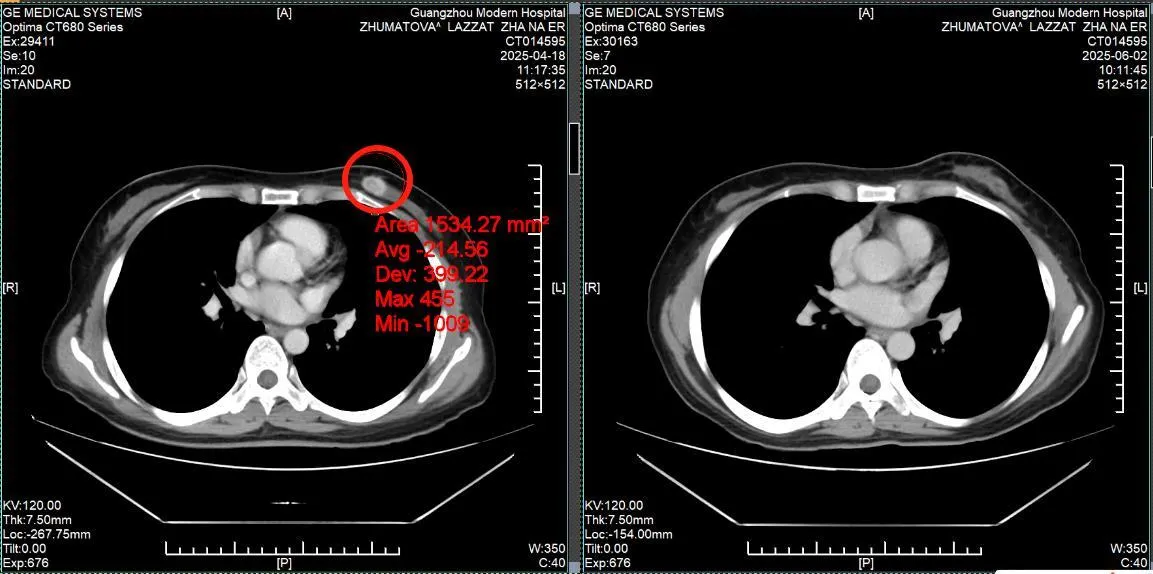

История пациента: Ляззат, 47 лет, юрист, Казахстан. Диагноз: Рак молочной железы IV стадии с множественными метастазами в печень. Тактика лечения: Комбинация интервенционной терапии (химиоэмболизация) и микроволновой абляции (МВА). Результат: Полная регрессия опухоли в молочной железе, уменьшение метастазов в печени более чем вдвое, нормализация функции печени и онкомаркеров. Неожиданная находка: когда привычный мир рухнул Ляззат - успешная женщина из Казахстана, юрист, привыкшая решать сложные задачи в суде, в начале 2025 года столкнулась с самым тяжелым делом в своей жизни. Обследование, начатое из-за усталости и скачков давления, привело к шокирующему открытию: во время УЗИ случайно обнаружили опухоль в печени, а вскоре она сама нащупала уплотнение в груди. Диагноз прозвучал как приговор: рак молочной железы IV стадии с множественными метастазами в печень. Местные врачи настаивали на единственном, по их мнению, варианте: длительном курсе химиотерапии и обязательной мастэктомии - удалении молочной железы. Принципиальное решение: сохранить не только жизнь, но и себя Для сильной и осознанной женщины это было неприемлемо. «Грудь - это не просто орган, это часть моей женской идентичности. Я никогда не соглашусь на ее удаление и должна найти лучшее решение», - так Ляззат сформулировала свою позицию. Она обратилась в клиники Турции, Индии, Южной Кореи, но нигде не получала гарантий, что лечение сможет победить рак и сохранить грудь. В момент отчаяния надежду подарила подруга, порекомендовавшая St.Stamford Modern Cancer Hospital Guangzhou и его малоинвазивные подходы.

Победа: возвращение к жизни и радости

Результат превзошел все ожидания. После двух курсов комбинированного лечения: • Опухоль в молочной железе полностью исчезла. • Метастатические очаги в печени уменьшились более чем в два раза. • Функция печени и уровень онкомаркеров (РЭА, СА153) пришли в норму. • Вернулись силы, ушла постоянная усталость. Уже в третий визит в Гуанчжоу Ляззат приехала одна, чувствуя себя настолько хорошо, что могла перенести длительный перелет и вернуться к привычной жизни. Ценить настоящее: урок, выученный с достоинством. Сегодня Ляззат не только победила болезнь, но и переосмыслила жизнь. Она благодарна команде врачей в Гуанчжоу за теплоту, поддержку и профессиональную помощь. Она активно практикует дыхательные методики и медитацию для борьбы со стрессом и участвует в жизни клиники. «Жизнь - это дар. У нас она только одна, и мы должны ее ценить, - говорит Ляззат. - Не следует переутомляться, злиться и беспокоиться. Живите настоящим и наслаждайтесь жизнью. В этом ее смысл!» Ее история - это вдохновляющий пример того, как современная медицина позволяет отстоять свое право на целостность и качество жизни даже в самой сложной ситуации.